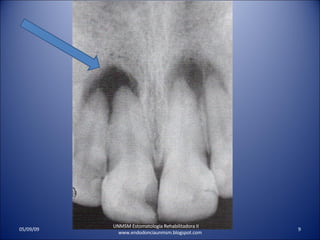

PERIODONTITIS PERIRRADICULAR CRONICA SIN SINTOMAS CLINICOS. NO RESPONDE A LA PRUEBA VITALIDAD P. RX. RADIOLUCIDEZ PERIRRADICULAR . INSENSIBLE A LA PERCUSION. EL PACIENTE LO SIENTE DIFERENTE A LA PERCUSION. UNMSM Estomatologia Rehabilitadora II  www.endodonciaunmsm.blogspot.com 06/10/09

PERIODONTITIS PERIRRADICULAR AGUDADOLOR AL MORDER. DOLOR A LA PERCUSION. RESPUESTA VARIABLE A LA VITALIDAD PULPAR. RX LIG. PERIODONTAL ENSANCHADO SIN RADIOLUCIDEZ PERIRRADICULAR UNMSM Estomatologia Rehabilitadora II www.endodonciaunmsm.blogspot.com 06/10/09

PERIODONTITIS PERIRRADICULAR CRONICASIN SINTOMAS CLINICOS. NO RESPONDE A LA PRUEBA VITALIDAD P. RX. RADIOLUCIDEZ PERIRRADICULAR . INSENSIBLE A LA PERCUSION. EL PACIENTE LO SIENTE DIFERENTE A LA PERCUSION. UNMSM Estomatologia Rehabilitadora II www.endodonciaunmsm.blogspot.com 06/10/09